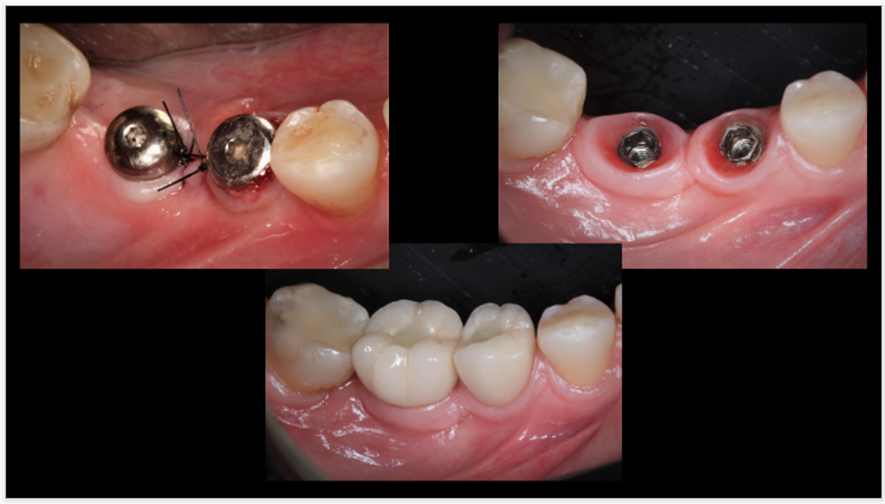

Neste caso clínico, a paciente C.X.M, sexo feminino, 46 anos, saudável, com histórico de doença periodontal, sem condições sistêmicas desfavoráveis e não-fumante, compareceu à clínica de especialização de Periodontia da UNIP. Após terapia periodontal, com a paciente apresentando saúde periodontal, foram instalados, na clínica de especialização, dois implantes do tipo HE, 4.0 X 6.0mm, Implacil De Bortoli. O acompanhamento deste caso clínico vem sendo realizado semestralmente na clínica de pós-graduação stricto sensu do programa de mestrado em Odontologia na área de Periodontia da UNIP, durante a terapia periodontal de suporte, nos últimos quatro anos.

Por meio deste caso clínico, podemos ilustrar que a instalação de implantes considerados curtos podem ter uma sobrevida longa com ótima estabilidade a longo prazo, corroborando as evidências científicas apresentadas acima, desde que todos os cuidados periodontais (terapia periodontal prévia à cirurgia de colocação do implante e terapia periodontal de suporte regular do paciente) sejam realizados.